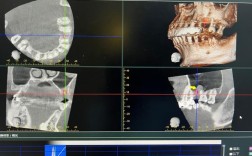

- 影像学检查: 拍摄X光片(根尖片、曲面断层片)和CBCT(锥形束CT),评估牙根位置、牙槽骨状况、种植体位置和角度、对颌牙伸长情况等,这是判断原因的关键。